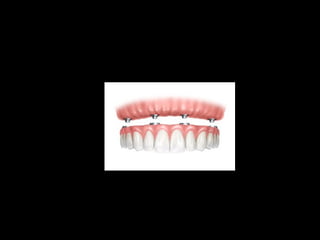

Colocación de la prótesis dentaria.